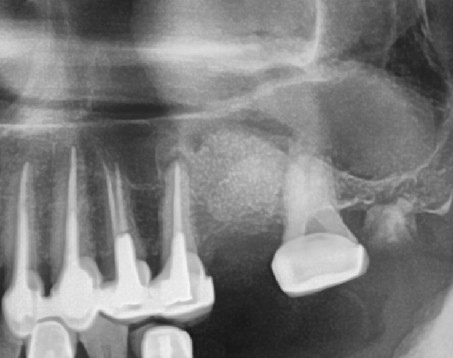

上顎竇增高(補骨)手術